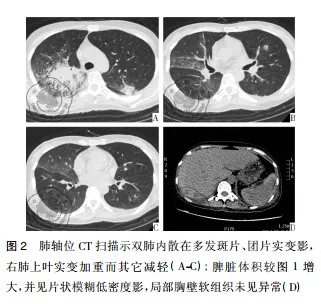

病例资料患者女性,42岁,因“咽痛、牙龈肿痛、发热20余天”于2017年5月13日入院。既往否认肝炎、结核及手术史。查体: 体温 37.8 ℃,贫血貌,齿龈增生,头颈部浅表淋巴结可触及肿大。咽部略充血、红肿,双肺、心脏、腹部查体未见异常。血常规: WBC 4.5×109 /L,RBC 2.23× 109 /L,PLT 67× 109/L,Hb 78 g /L,中性粒细胞绝对值( NE#) 0.22×109 /L。入院后给予抗炎治疗,体温降至正常。经骨髓活检确诊为急性髓系白血病 AML-M5( 中危组) ,于2017 年5月16日起行( 去甲氧柔红霉素+阿糖胞苷) 方案化疗。化疗间歇第14天,骨髓象未缓解,患者出现间断发热,炎性指标超敏C反应蛋白升高,肺CT提示肺内感染、脾脏未见异常,见图 1。故采用伏立康唑加亚胺培南联合抗炎治疗。化疗间歇第21天,骨髓象部分缓解。2017 年 6 月 26 日起给予方案强化巩固治疗。第二化疗间歇第8天,患者出现发热,体温达 39 ℃,伴寒战、大汗,超敏C反应蛋白 47.20 mg /L,降钙素原 19.81 ng /ml,痰培养见肺炎克雷伯菌肺炎亚种,复查肺CT提示肺内感染加重。先后给予美洛培南、阿米卡星、伏立康唑、替考拉宁、泊沙康唑、万古霉素及左氧氟沙星抗感染治疗。第二化疗间歇第16天,患者出现左季肋部疼痛,腹部彩超未见明确异常。腹部CT显示脾实质不均匀低密度伴周围渗出,见图 2。给予抗炎及对症治疗,患者仍间断发热及左季肋部疼痛。第二化疗间歇第 57 天,患者左侧肋下局部软组织隆起,皮肤变红及皮温升高,1周后左侧肋下包块破溃,流黄白色脓液及偶伴臭味,脓汁真菌涂片查到真菌孢子。胸腹部 CT提示肺内真菌感染,见图 3; 脾实质内液气混杂密度影,蔓延至左侧胸腹壁,累及结肠脾曲、左肾实质,伴左侧第10-11肋骨骨质破坏,见图4。遂于2017年9月18日全麻下行剖腹探查术,术中见腹腔大量脓液及粪便,胃、脾表面被覆脓苔,脾脏体积小,脾脏结肠瘘。遂行脾切除术、左侧腹壁窦道切除、结肠脾曲部分切除、肠吻合术及回肠造瘘术,并行胃部分切除术。术后病理示脾坏死、结肠穿孔,坏死周围及穿孔区周围、胃壁浆膜及肌层见大量急慢性炎细胞浸润、脓肿形成、肉芽组织及纤维增生,伴多核巨细胞反应及坏死样物,见图 5。患者病程中白细胞计数及超敏C反应蛋白变化过程如图 6 所示。术后患者恢复较好,进食、排气排便正常,于9月27日顺利出院。